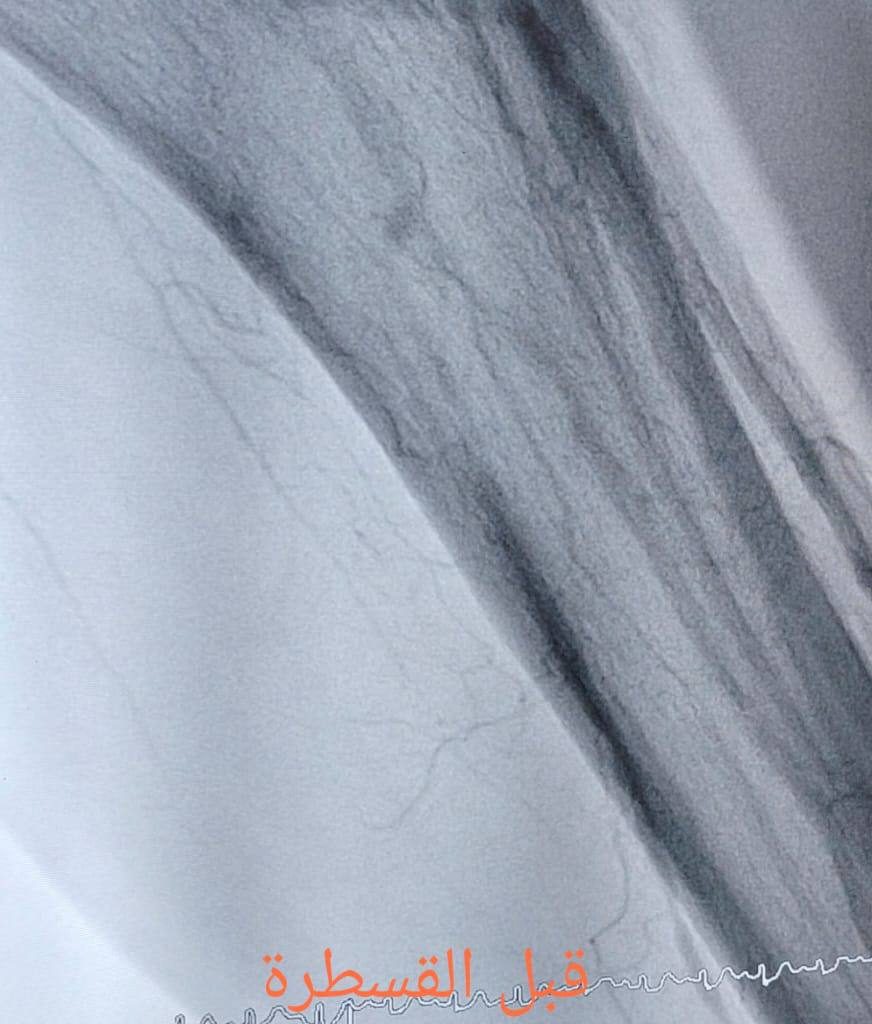

“استقبلنا حالتين لمريض ومريضة في السبعينات من العمر، كانا يعانيان من انسداد كامل في شرايين الساقين نتيجة تصلب الشرايين، مع وجود قدم سكري وبداية حدوث كانكرين؛ إحداهما في الساق الأيسر والأخرى في الساق الأيمن.”

“تم إجراء عمليتين للقسطرة الشريانية، حيث عملنا على فتح الانسدادات في الشرايين الطرفية وعلاج قصور الشرايين، ما ساهم في إعادة جريان الدم إلى الساقين والقدمين بعد أن كانت الحالتان مهددتين بالبتر.”